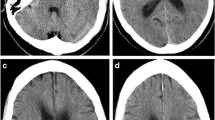

The measurement of T2-SI and ADC value was performed at five locations set in each ROI (Fig. 1). Each T2-SI or each ADC value was normalized by the corresponding contralateral area (non-ischemic location in the right hemisphere), which was expressed as the ratio of ipsilateral to contralateral values.

The location of each ROI. Left: The result of a TTC stain on a brain section. Right: T2-weighted image of the section selected on the left. Four ROIs were set in the left cortex (the reference was set in the corresponding right cortex) as shown on the left. ROI-1, ischemic core, where cells are dead; the dead zone. ROI-2, medial border zone including the ischemic penumbra, where some cells are dying or dead; the mixed zone of dying/dead. ROI-3, lateral border zone excluding the ischemic penumbra; the surviving zone. ROI-4, intact zone, the area without ischemic stress; the non-ischemic zone

The TTC Stain Index

Individual densities of the TTC stain at different ROIs are shown in Fig. 2a. The ischemic core (ROI-1), the ischemic penumbra (ROI-2), and the survived (lateral border) zone (ROI-3) showed significant reductions compared to the corresponding contralateral area (control). The reduction levels in ROI-2 was significantly stronger than ROI-3, but significantly weaker than ROI-1, indicating that the death ratio (the final survivability index) of the tissue in each ROI related to ischemia was confirmed to represent the individual significance.

a The densities measured in each ROI after the TTC stain at 24 h post-reperfusion. The density in each ROI was significantly different, indicating that the individual ROIs possessed a quantitatively different survivability of the tissue with a different destiny. Alterations in the T2-SI ratio (T2-SI) after focal ischemia/reperfusion. b The T2-SI increased rapidly after induction of ischemia/reperfusion in every ischemic zone (ROI-1, ROI-2, ROI-3). An increase in the T2-SI in the surviving zone, interpreted as benign vasogenic edema, achieved a significant increase, at 1, 1.5, 2, and 3.5 h and thereafter, compared to the contralateral control. The T2-SI in the medial border zone (including the ischemic penumbra) achieved a significant increase at 2.5 h and thereafter, while the T2-SI in the ischemic core, interpreted as malignant vasogenic edema, achieved a significant increase at 4 h post-reperfusion. c Comparisons between the zone with irreversible tissue damage (including cellular death at 24 h post-reperfusion) and the zone without irreversible tissue damage (no death at 24 h post-reperfusion). There was no significant difference in the T2-SI, except at 3.5 h post-reperfusion, when vasogenic edema was more severe in the surviving zone. p < 0.001 vs. contralateral control (one-way ANOVA)